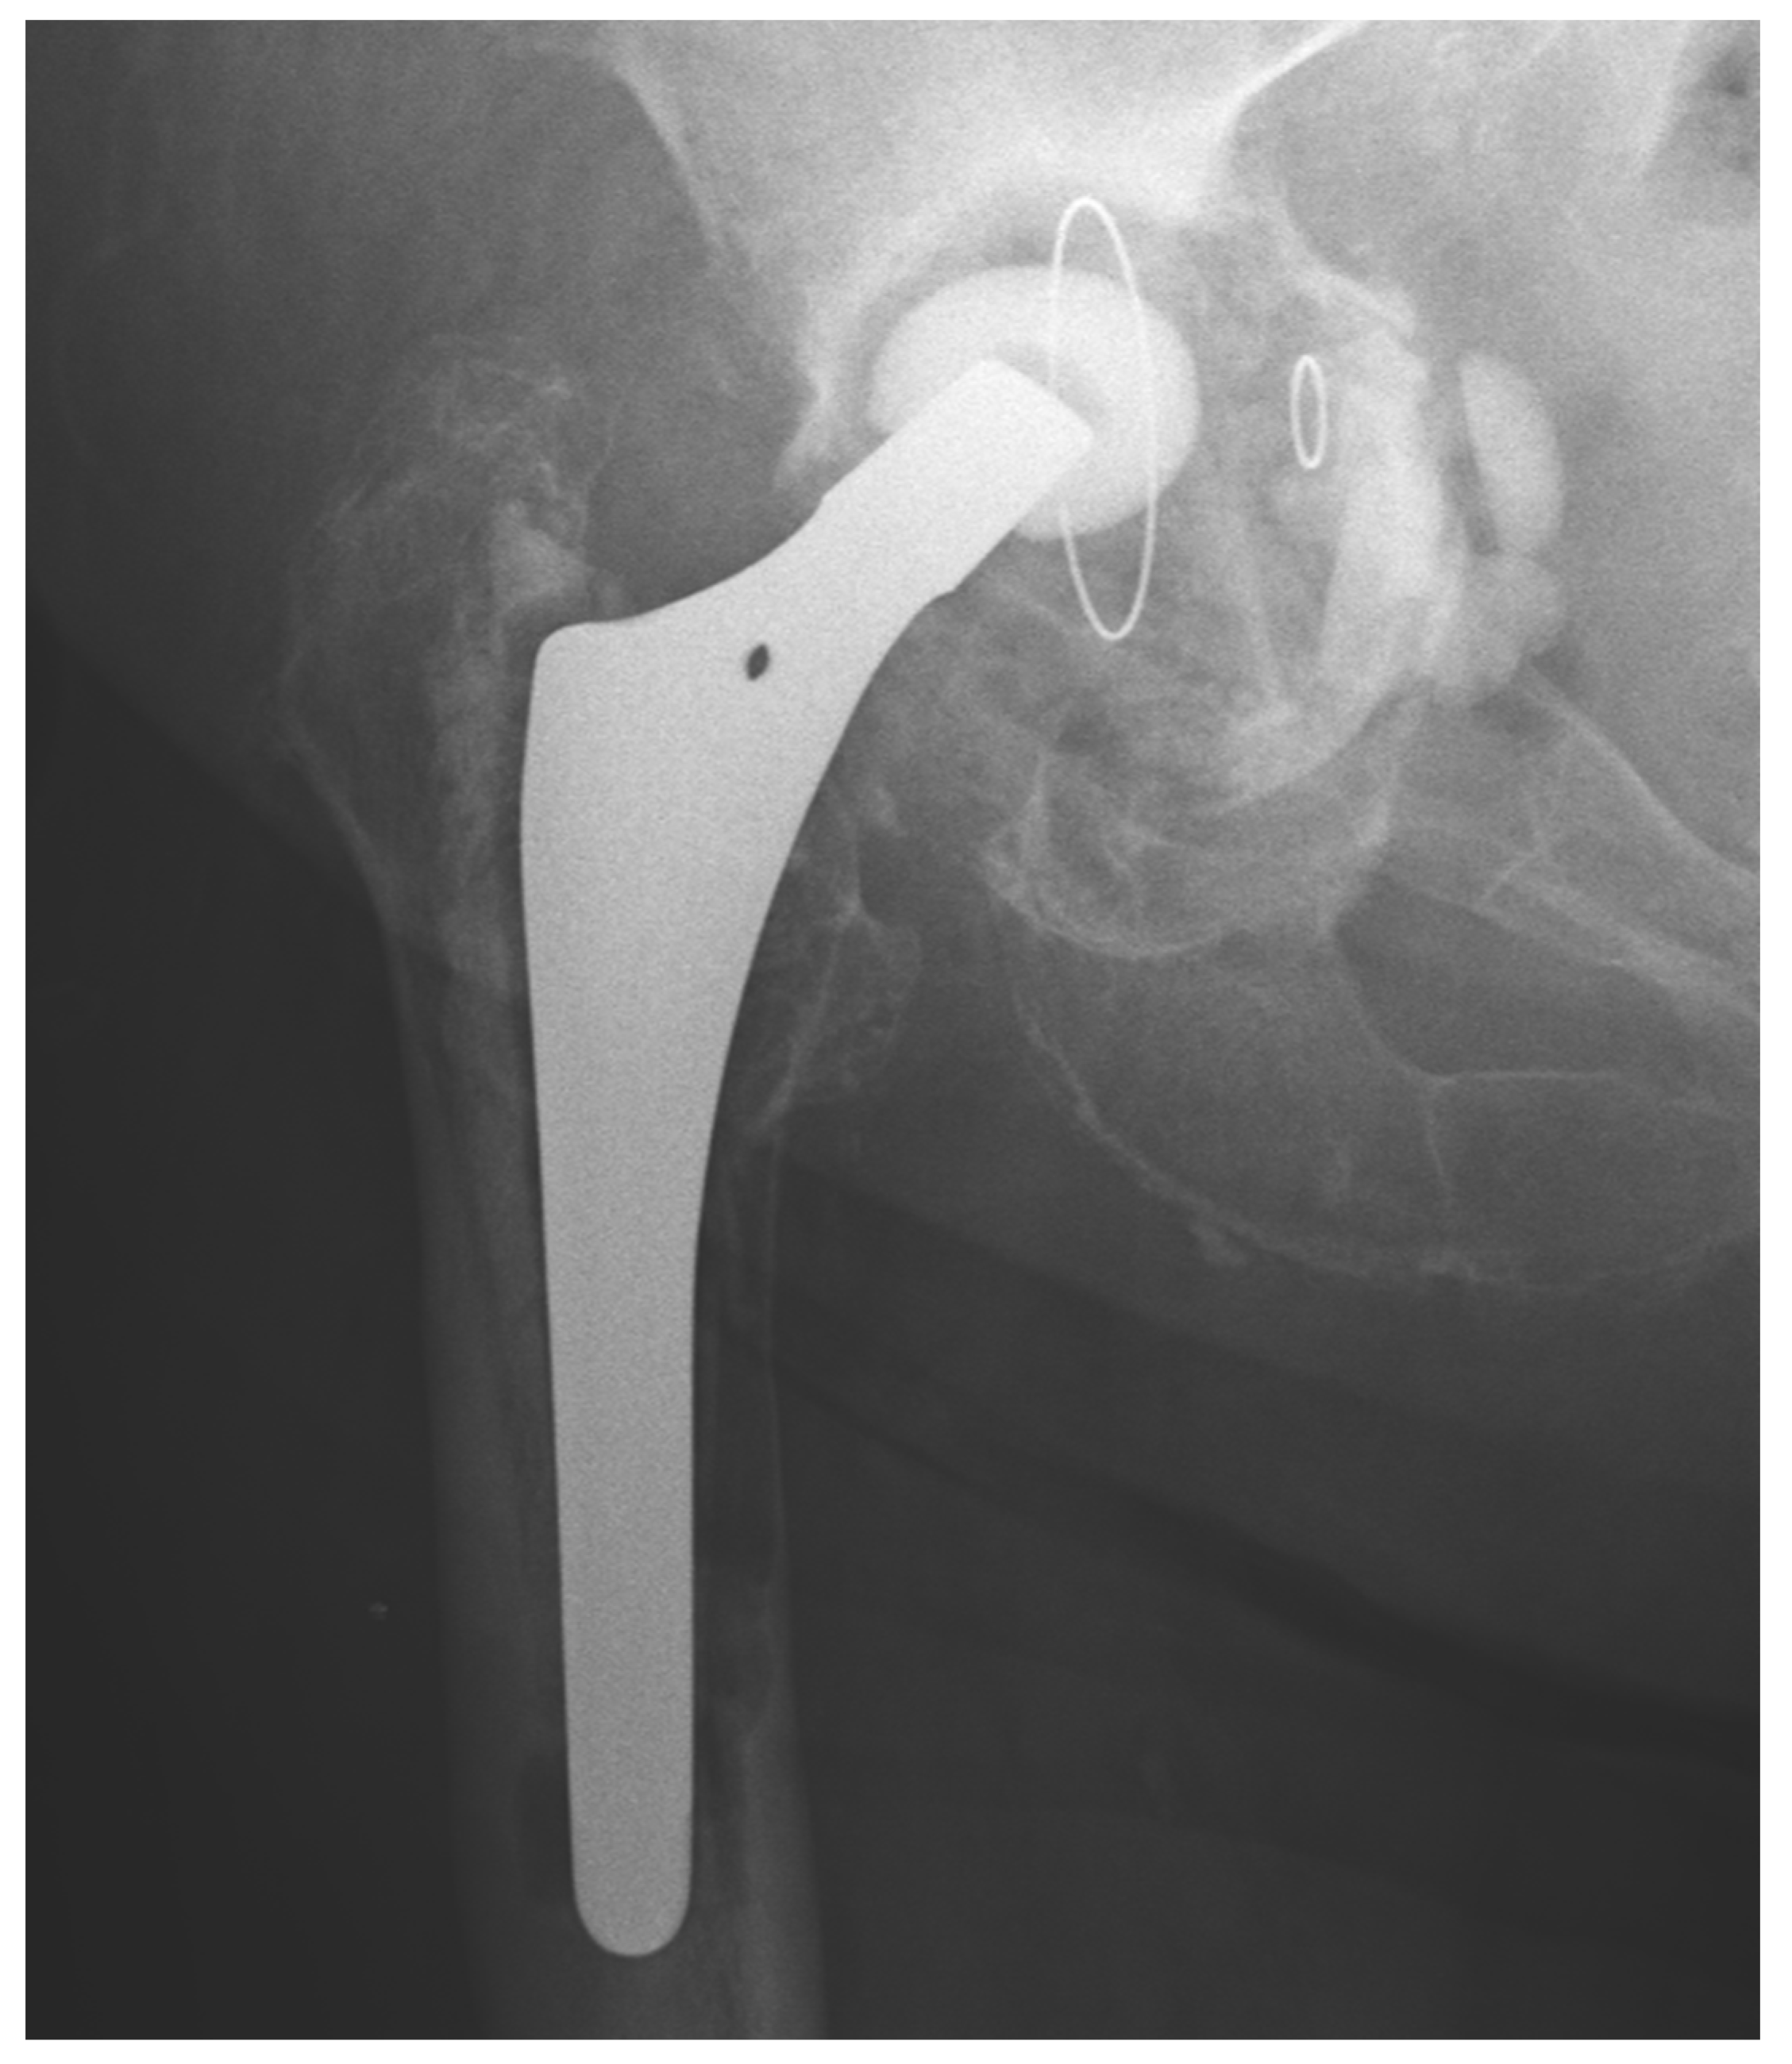

We observed a positive correlation between the increase in the mean oxidation index (OI) of the bearing surface of the inlays and the extent of periacetabular osteolysis classified according to the Paprosky scale (R = 0.44; p = 0.011). The most commonly revised types were 3A and 2B: 12 out of 33 samples (36.36%) were classified as type 3A, and 7 out of 33 samples were classified as type 2B (21.21%) according to Table 2. Mean oxidation index values for each type are, respectively, presented in Table 3. Figure 1 illustrates the differences in oxidative indices between the control sample and selected samples from groups 1 and 3B. Attention should be paid to the difference in the spectrum range of 1685–1745 cm−1. Representative X-ray images of patients depicting the extent of osteolysis based on the Paprosky scale can be seen in Figure 2, Figure 3 and Figure 4.

Figure 2. Periacetabular osteolysis classified as Paprosky 1.

Figure 3. Periacetabular osteolysis classified as Paprosky 2B.

Figure 4. Periacetabular osteolysis classified as Paprosky 3B.